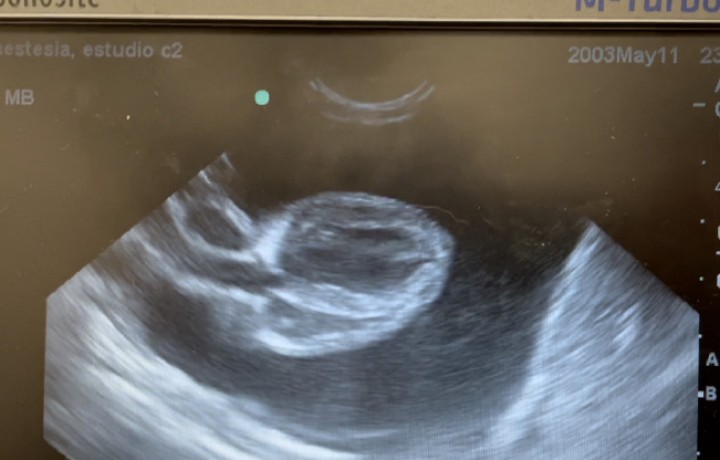

<p><strong>Ecografía</strong>. La hipotensión es una complicación común durante la anestesia. La utilización de ecografía puede ser de utilidad para descartar algunas de las diferentes causas, como puede ser una hipovolemia o una hipocontractibilidad miocárdica. En ocasiones podemos encontrar causas más infrecuentes, como en este caso en que se observa un taponamiento cardíaco por efusión pericárdica. En este paciente, el ECG realizado durante la monitorización anestésica también nos habría hecho sospechar al mostrar una alternancia eléctrica. El uso de ecografía durante la anestesia se está extendiendo cada vez más en veterinaria debido a que puede ayudarnos a diagnosticar el origen de complicaciones cardiovasculares y ventilatorias. En este caso, el drenaje y aumento de la volemia mejorará el estado cardiovascular del animal.</p>

Ecografía. La hipotensión es una complicación común durante la anestesia. La utilización de ecografía puede ser de utilidad para descartar algunas de las diferentes causas, como puede ser una hipovolemia o una hipocontractibilidad miocárdica. En ocasiones podemos encontrar causas más infrecuentes, como en este caso en que se observa un taponamiento cardíaco por efusión pericárdica. En este paciente, el ECG realizado durante la monitorización anestésica también nos habría hecho sospechar al mostrar una alternancia eléctrica. El uso de ecografía durante la anestesia se está extendiendo cada vez más en veterinaria debido a que puede ayudarnos a diagnosticar el origen de complicaciones cardiovasculares y ventilatorias. En este caso, el drenaje y aumento de la volemia mejorará el estado cardiovascular del animal.